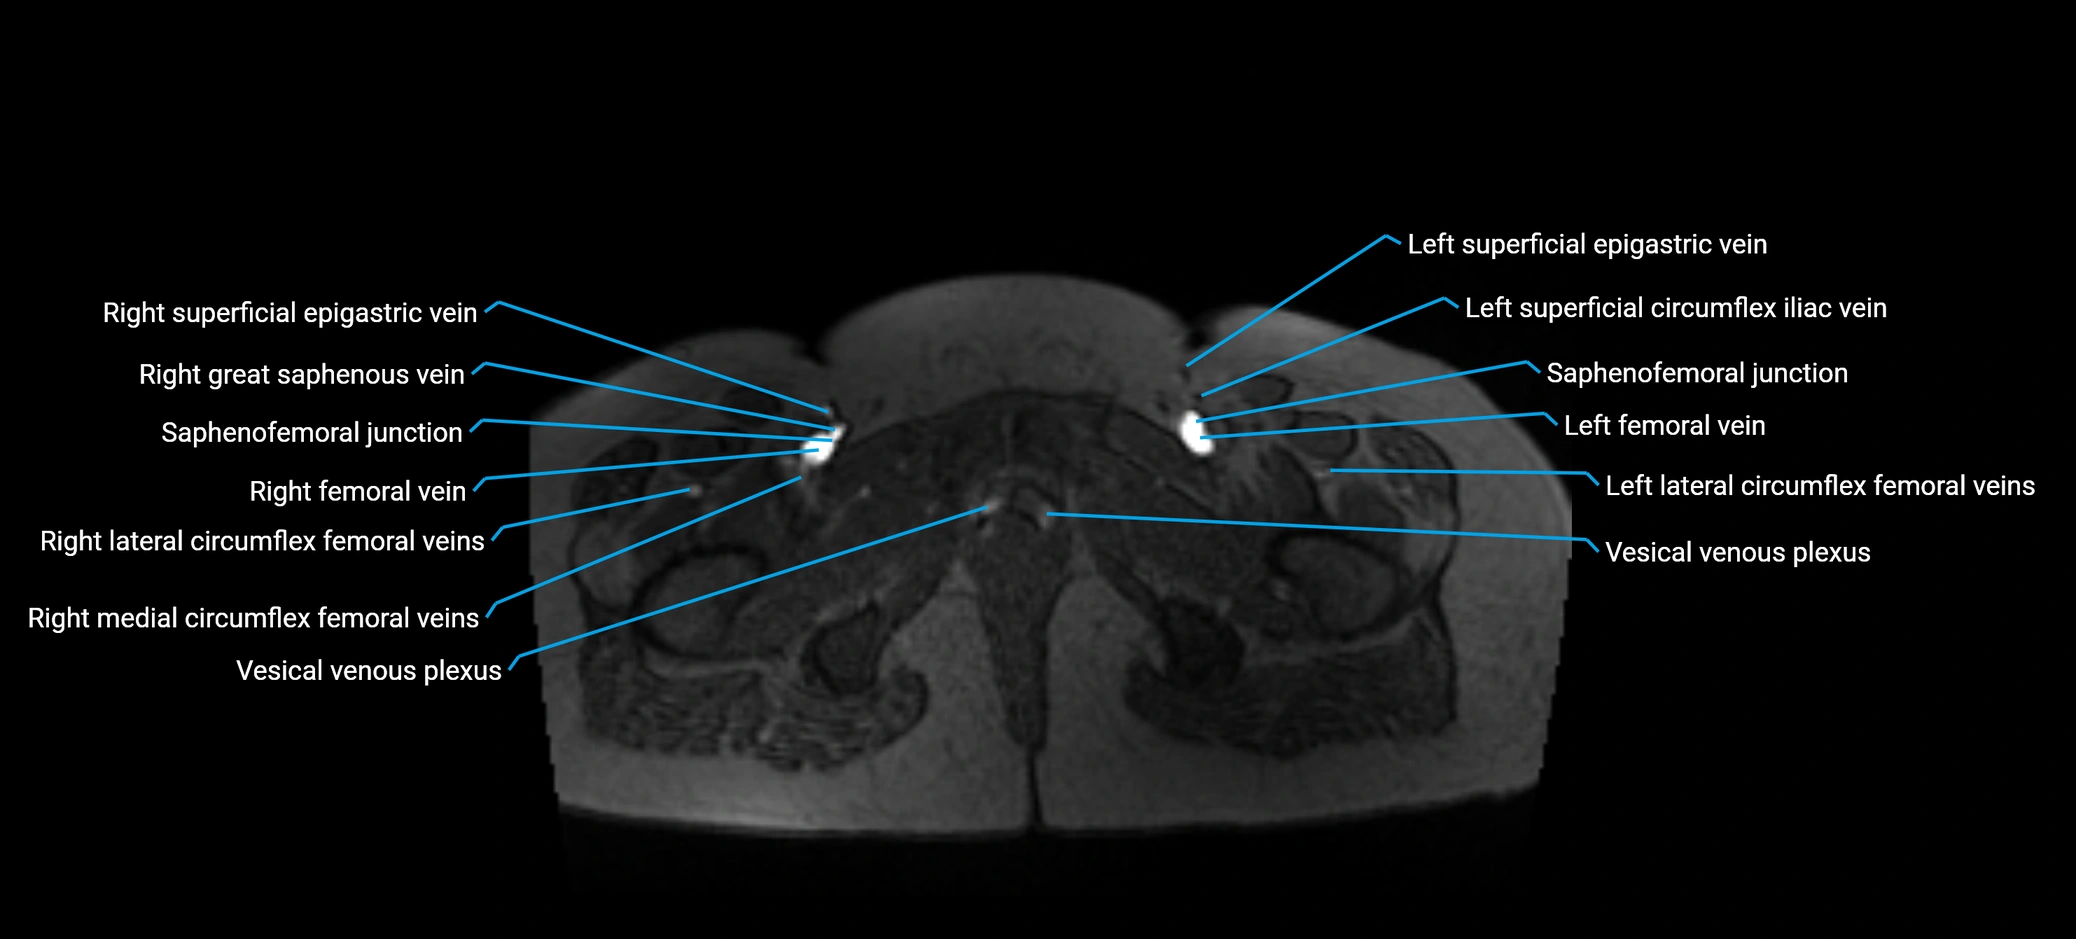

MRI image

image